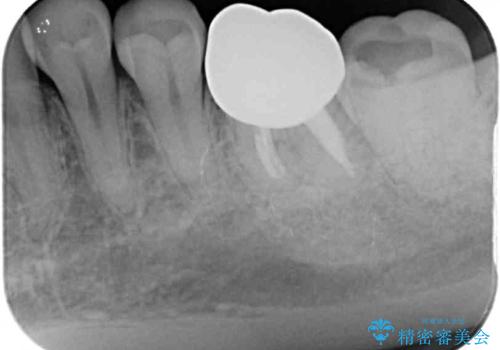

- 近医にてセラミックを装着した左下の奥歯に痛みが続いたとのことで来院された患者様です。

診査の結果、既に歯の神経は失活していたおり、排膿路が認められ、叩いたり触ったりしたときの痛みも確認されました。

根管治療を行った後にオールセラミッククラウンにて補綴することとしました。

初回の治療後には歯肉に認められた排膿の出口などの症状は消えていました。

補綴後6ヶ月経過しレントゲンを撮影したところ、遠心の歯根付近の病変が消失していることが確認できました。